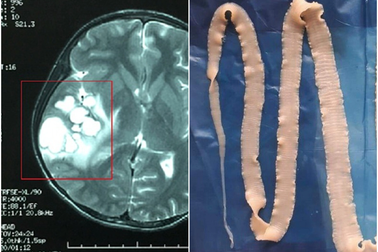

Báo động: Nhiều người nhiễm loại giun dài tới 120cmĐến nay, Việt Nam ghi nhận 24 trường hợp nhiễm giun rồng. Đây là loài mới xuất hiện ở nước ta, là một trong những loại giun dài nhất ký sinh trong cơ thể người, với chiều dài 70-120cm.

Sán làm tổ trong não vì 3 món nhiều người Việt thường ănChụp cộng hưởng từ sọ não thấy khối tổn thương ký sinh tại vùng não của bệnh nhân do ấu trùng sán dây lợn.